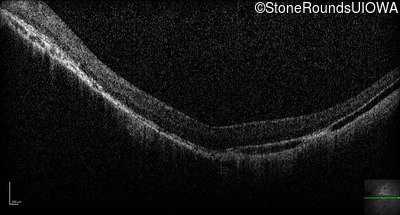

Optical Coherence Tomography - Right - 20/200 -1

Exemplar / OCT Stack

OCT Stack

Optical Coherence Tomography - Left - 5/160